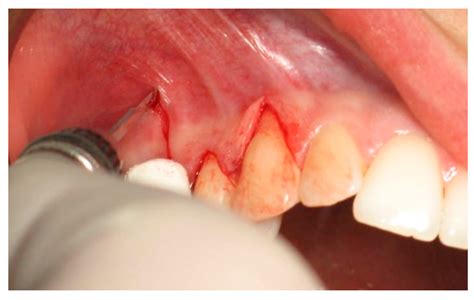

A flap in gums occurs when the gum tissue pulls away from the tooth, exposing the root. This can lead to various issues, including sensitivity, pain, and an increased risk of tooth decay. The condition can be caused by several factors, including poor oral hygiene, gum disease, and aggressive brushing.

• Visible Recession: The gum tissue appears to be pulling away from the tooth, exposing the root.

• Bleeding: Gums may bleed during brushing or flossing.